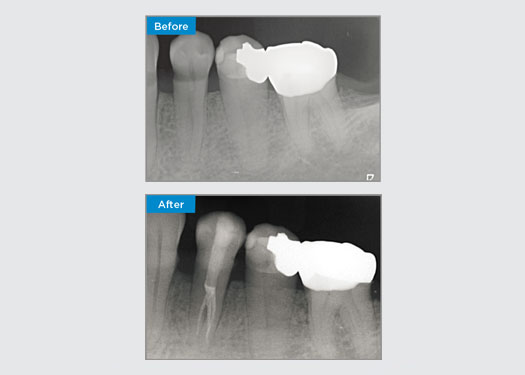

The patient presented with asymptomatic apical periodontitis on tooth 34. From the pre-op radiograph, tooth 34 was noted with two visible roots. However, a CBCT scan confirmed a three rooted premolar, and the canals divided into three at the mid root. A careful file selection is critical for this delicate tooth.

Dr Jack Lin, Endodontist, Sydney, NSW Australia

In this situation, tooth/root structure preservation is essential to reduce the risk of ledging, transportation, zipping, perforation, and root fracture. Case selection, diagnosis, and pre-treatment planning are important. Endodontic file selection with flexibility, efficiency, and respect of natural root anatomy is critical.